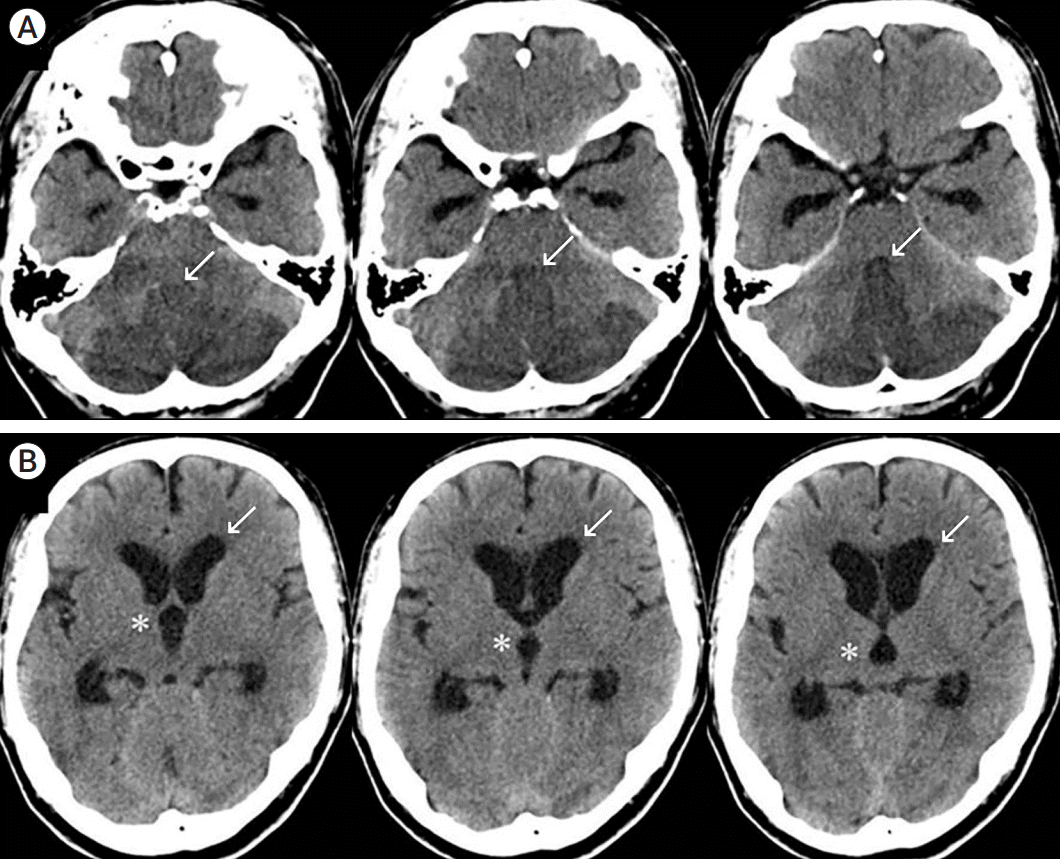

Fig. 1.

A 65-year-old male patient with acute cerebellar infarction. (A) Brain CT at admission shows acute cerebellar infarction with obstruction of the fourth ventricle (arrows) and mild brain stem compression. The infarction volume is 30.9 ml. (B) CT shows third ventricle dilatation (asterisks) and lateral ventricle anterior horn dilatation (arrows). CT, computed tomography